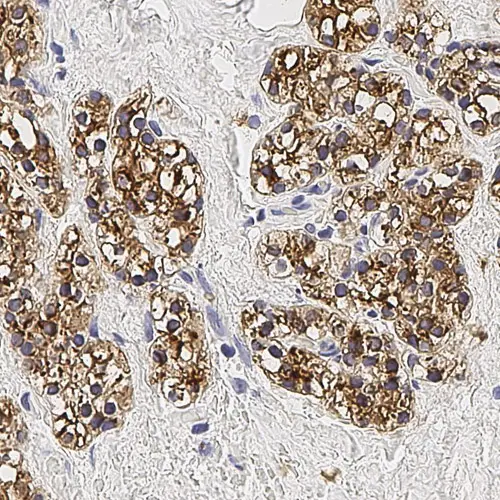

Human parathyroid adenoma: immunohistochemical staining for Parathyroid Hormone. Note membrane/cytoplasmic staining of tumor cells. Parathyroid Hormone: clone 105G7

Parathyroid Hormone (PTH) is recommended for the detection of specific antigens of interest in normal and neoplastic tissues, as an adjunct to conventional histopathology using non-immunologic histochemical stains.